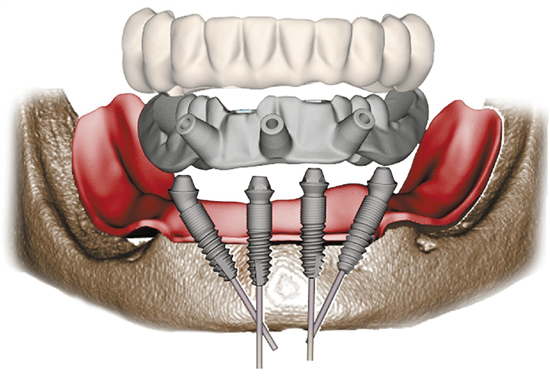

“这个您不用担心。”海涛口腔种植科唐主任经过口内数据分析和会诊后告诉李大妈:“我们借助计算机,设计出您口腔内8个适合种植的位置,利用海涛“一天得”全口种植牙技术,上下半口各4颗种植体就能分别完成半口牙修复,恢复全口咀嚼功能。”

更少的种植体+无需植骨+精准的力学设计,当天种出一口新牙

海涛口腔唐主任介绍,海涛“一天得”全口种植牙是海涛口腔的特色技术,数字化导航定位,植入精准,只需植入4颗或6颗种植体就可以解决半口无牙问题,并且当天种牙,当天就可戴牙吃饭。整个手术过程一次性完成,大大缩短了患者的就诊时间和次数,节省了治疗费用,价格相比传统种植牙省了很多。同时,该技术采用2毫米的钛丝,结合国际先进的口内冷焊接技术焊接而成,稳定性非常好。与此同时,该技术打破传统种植技术瓶颈,破解牙槽骨萎缩、骨量不足等种植难题,无需植骨不增加额外费用,让这一缺牙群体也能实现种植牙。